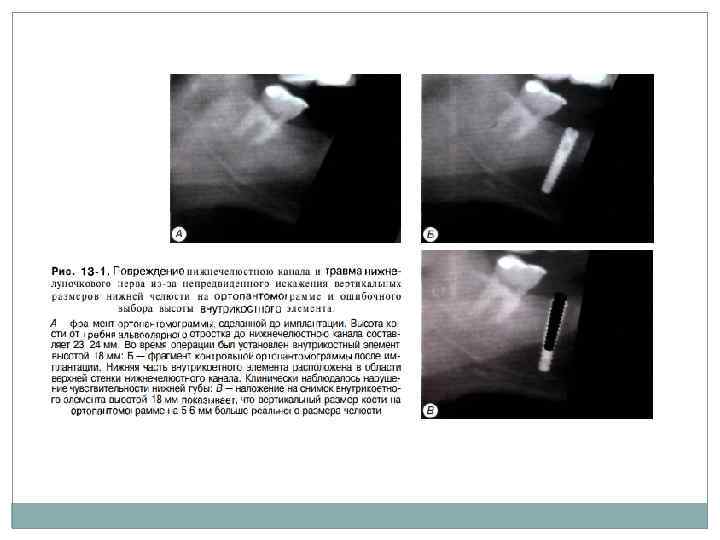

Осложнения во время имплантации 1. Перелом инструмента ( причина – чрезмерный нажим на инструмент во время продольного сверления ложа имплантата (чаще фиссурные боры во время препарирования костного ложа под пластиночный имплантат); неправильный температурный режим стерилизации). 2. Пенетрация дна верхнечелюстной пазухи и полости носа (причины: неправильное определение высоты альвеолярного отростка по ОПТГ, чрезмерное давление на инструмент, небрежное препарирование костного ложа). 3. Повреждение стенок нижнечелюстного канала и травма нижнелуночкового нерва (некорректное планирование лечения, небрежное препарирование костного ложа, неправильное определение размеров имплантата из за непредвиденного искажения вертикального размера нижней челюсти на ОПТГ). Следует отметить, что не всегда вскрытие стенки нижнечелюстного канала обязательно вызывает необратимое повреждение нижнелу ночкового нерва. Вскрытие стенки канала может привести к образованию внутриканальной гема томы и с давлению нерва. В этом случае частично утраченная чувствительность в зоне иннервации иижнелуночкового нерва постепенно восстанав ливается в течение 2 3 х недель»